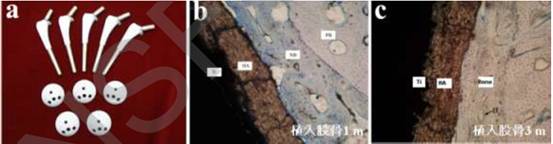

羟基磷灰石涂层是指以钛合金为基底,利用物理化学手段将羟基磷灰石涂覆在其表面制备的硬组织植入材料。该材料植入人体后,钛合金可以提供足够的力学强度,表面的羟基磷灰石涂层易于与人体骨结合,在人体骨表面诱导新骨的生成,一般数月即可诱导新骨的生成。中国科学院上海硅酸盐研究所利用等离子喷涂技术制备的羟基磷灰石涂层,涂层与基底结合强度高,生物活性好,并已应用于人工髋关节等部位,至今制备的羟基磷灰石涂层植入体已有7万余付获得应用,取得了不错的临床效果,如图1所示。但羟基磷灰石涂层存在结合力不够强的缺点,以至于在体内植入后出现涂层脱落的现象,这种问题的解决办法目前仍在不断的探索中。

图1. 部分临床应用的羟基磷灰石涂层骨替代材料与体内成骨实验。(a)羟基磷灰石涂层人工髋关节;(b)植入1月后,新骨生成并填充涂层与骨组织之间的孔隙;(c)植入3月后,新骨被成熟的骨组织替代。